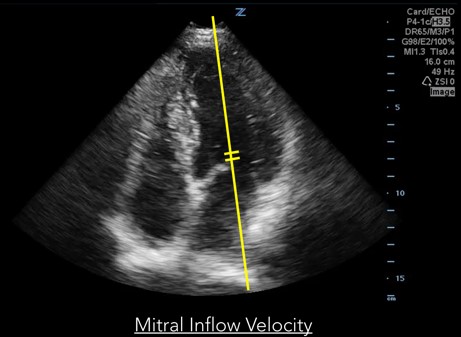

Measurements of diastolic function are obtained using Spectral Doppler to measure blood and tissue velocities. Pulsed wave Doppler uses the Doppler effect to allow assessment of both blood and tissue velocity and direction. The sample gate of the pulsed wave Doppler is placed between the tips of the mitral valve leaflets to measure blood velocity. (Figure 1) In addition to pulsed wave Doppler, tissue Doppler imaging setting is used to measure tissue velocity, and to determine the compliance of LV tissue during diastole. Tissue Doppler imaging filters out higher velocity signals to improve imaging of lower tissue velocities. With Tissue Doppler, the sample gate is placed in either of two locations: at the septal mitral annulus or at the lateral mitral annulus. (Figure 2) All measurements are performed on the apical four chamber view.

Fig 1. Mitral inflow velocity